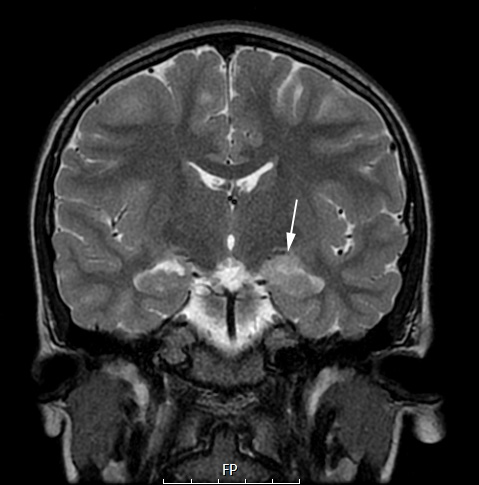

The lesion is slightly more intense on this coronal T2-weighted non-contrast scan. In some cases the scan has a more nodular appearance.